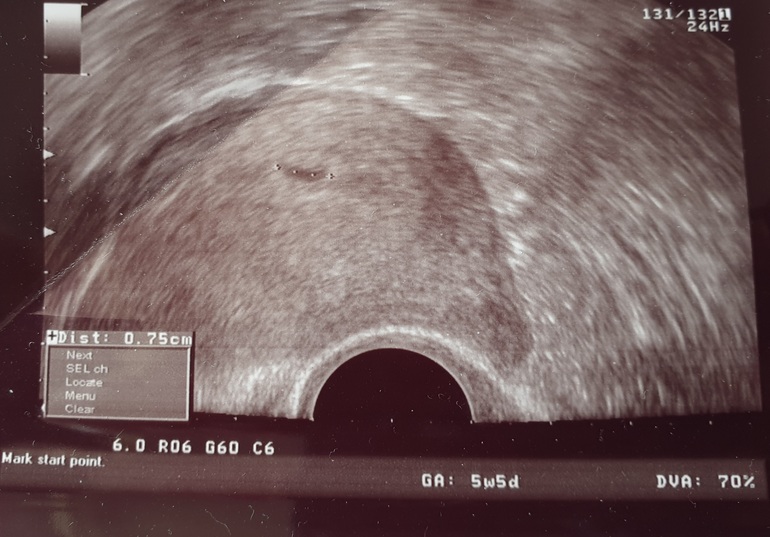

Просто приложу снимок нашего второго УЗИ без сердцебиения, эмбриона и никаких шансов на нормальную беременность в 5 недель 3 дня

P.s. Нам сегодня 20 неделек)))